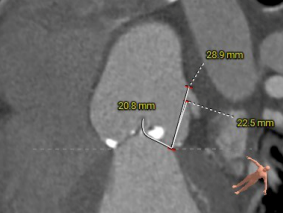

左窦瓣叶长度:20.8mm

右窦瓣叶长度:19.1mm

左冠开口高度:21.4mm

右冠开口高度:16.3mm